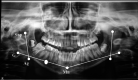

Materials and method: Fifteen patients of prospective study design were selected for study. This study was undertaken to evaluate the mandibular ramal growth in TMJ ankylosis patients treated without growth center transplantation using orthopantomogram as a tool of assessment.

Results: Mean ramal length of the operated right side was found to be 42.02 mm in immediate postoperative, 43.18 mm in sixth month postoperative and 44.57 mm in 1 year postoperative follow-up. Mean ramal length of the operated left side was found to be 40.15 mm in immediate postoperative, 42.10 mm in sixth month postoperative and 44.80 mm in 1 year postoperative follow-up.